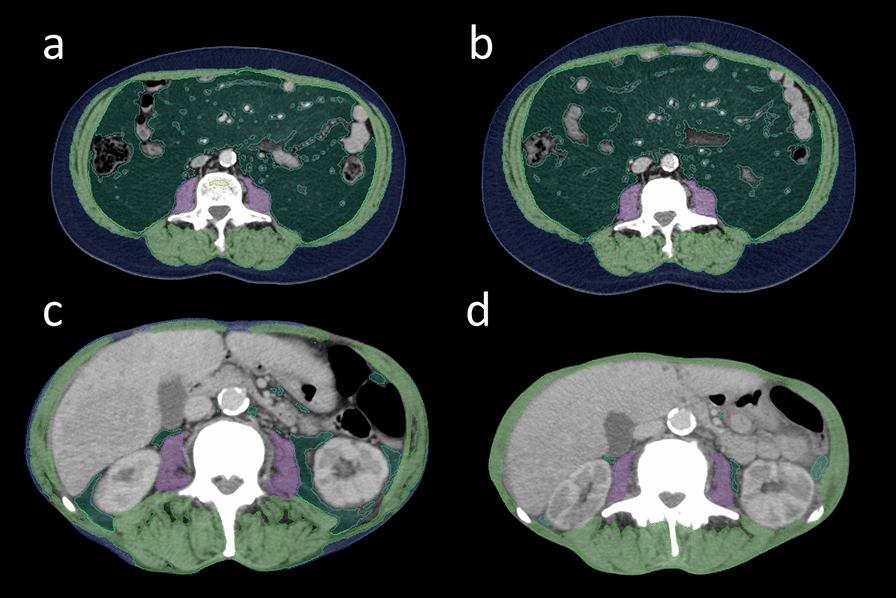

Background: Body composition (BC) analysis is performed to quantify the relative amounts of different body tissues as a measure of physical fitness and tumor cachexia. We hypothesized that relative changes in body composition (BC) parameters, assessed by an artificial intelligence-based, PACS-integrated software, between baseline imaging before the start of radioligand therapy (RLT) and interim staging after two RLT cycles could predict overall survival (OS) in patients with metastatic castration-resistant prostate cancer.

Methods: We conducted a single-center, retrospective analysis of 92 patients with mCRPC undergoing [177Lu]Lu-PSMA RLT between September 2015 and December 2023. All patients had [68 Ga]Ga-PSMA-11 PET/CT at baseline (≤ 6 weeks before the first RLT cycle) and at interim staging (6-8 weeks after the second RLT cycle) allowing for longitudinal BC assessment.